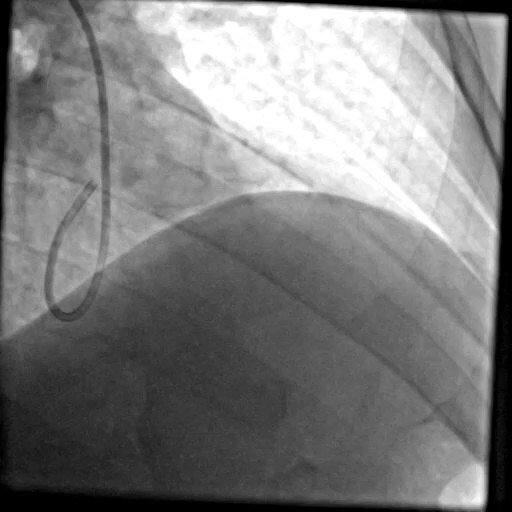

LAD proximal CTO with LM trifurcation, angiographic image View on X

LAD prox CTO LM trifurcation CABG declined

LAD proximal CTO with LM trifurcation disease

Patient declined surgical revascularization. Single transradial 8F access with EBU 3.5 guide for adequate backup. The case illustrates strategic guide selection and access planning when committing to PCI of a left main bifurcation/trifurcation in the setting of a proximal LAD CTO.

Artery: LAD prox + LM

Access: Radial 8F

Guide: EBU 3.5

Setting: CABG turndown